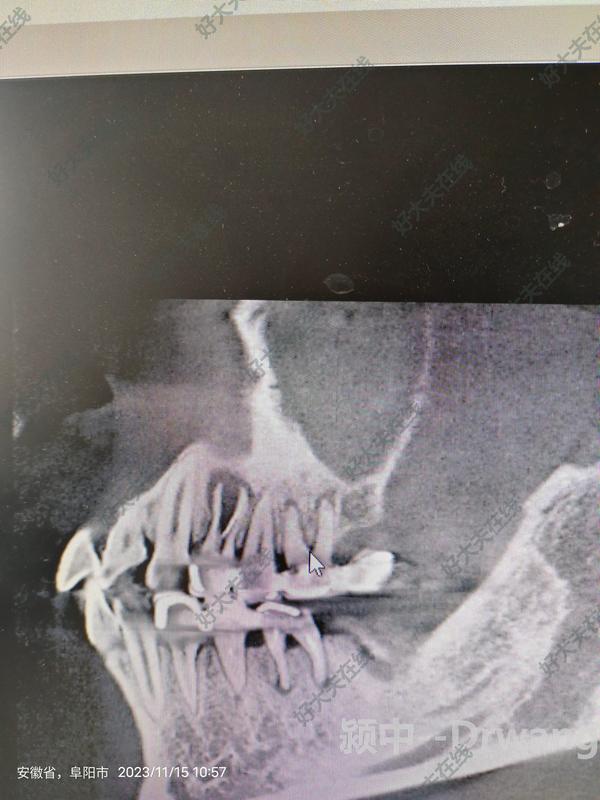

慢性根尖周炎

牙齦上的小包不要忽略(溢膿,紅腫,不是上火,可能是根尖周炎)

有些人,牙齒疼的時候,吃不下飯,睡不著。然后,突然不疼了。就覺得好了。其實,反而是病情變嚴(yán)重了。今天這位姑娘的牙齒就是這樣,牙齦一個大包,反而不疼了。其實,壞掉的牙神經(jīng),等于把牙齦下面的骨頭,腐蝕了一個大洞。所以,牙齦上的小包,不要大意。再不看,這個大洞,要往上,會影響鼻咽,甚至上頜骨了。。。